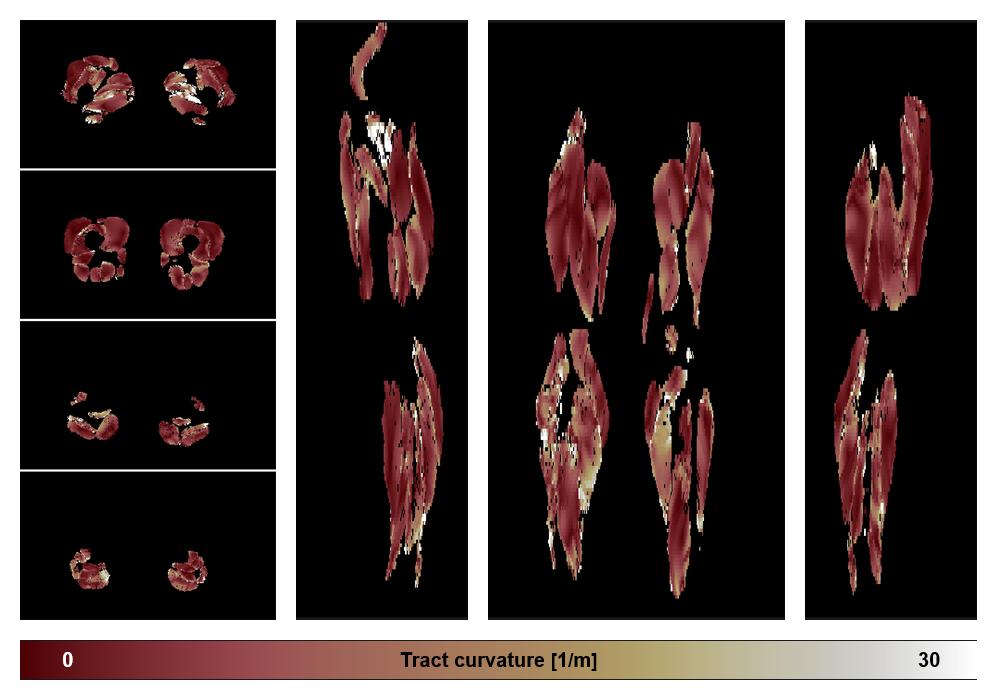

• Muscle fiber curvature map

Muscle fiber tract curvature map based on whole leg DTI based fiber tractography.